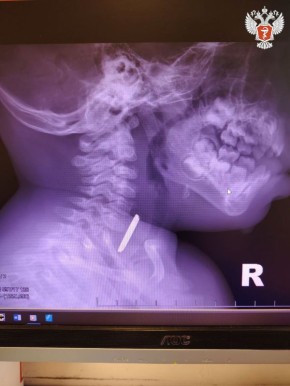

Годовалый ребенок поступил в Нижневартовскую окружную клиническую детскую больницу с затруднённым глотанием и слюнотечением. Врачи выполнили рентген и выявили круглое инородное тело в верхней трети пищевода.

Специалисты приняли решение о проведении экстренной операции и извлекли батарейку, но предмет успел нанести вред здоровью пациента.

— Батарейка повредила стенку пищевода, вызвав глубокий электрохимический ожог, занимающий половину просвета пищевода. Учитывая тяжесть состояния от полученной травмы, ребенок был госпитализирован в отделение реанимации, где проводилась интенсивная терапия. После стабилизации состояния малыша перевели в детское хирургическое отделение, где было продолжено ранее начатое консервативное лечение, — рассказал детский хирург Нижневартовской окружной клинической детской больницы Вячеслав Воронин.